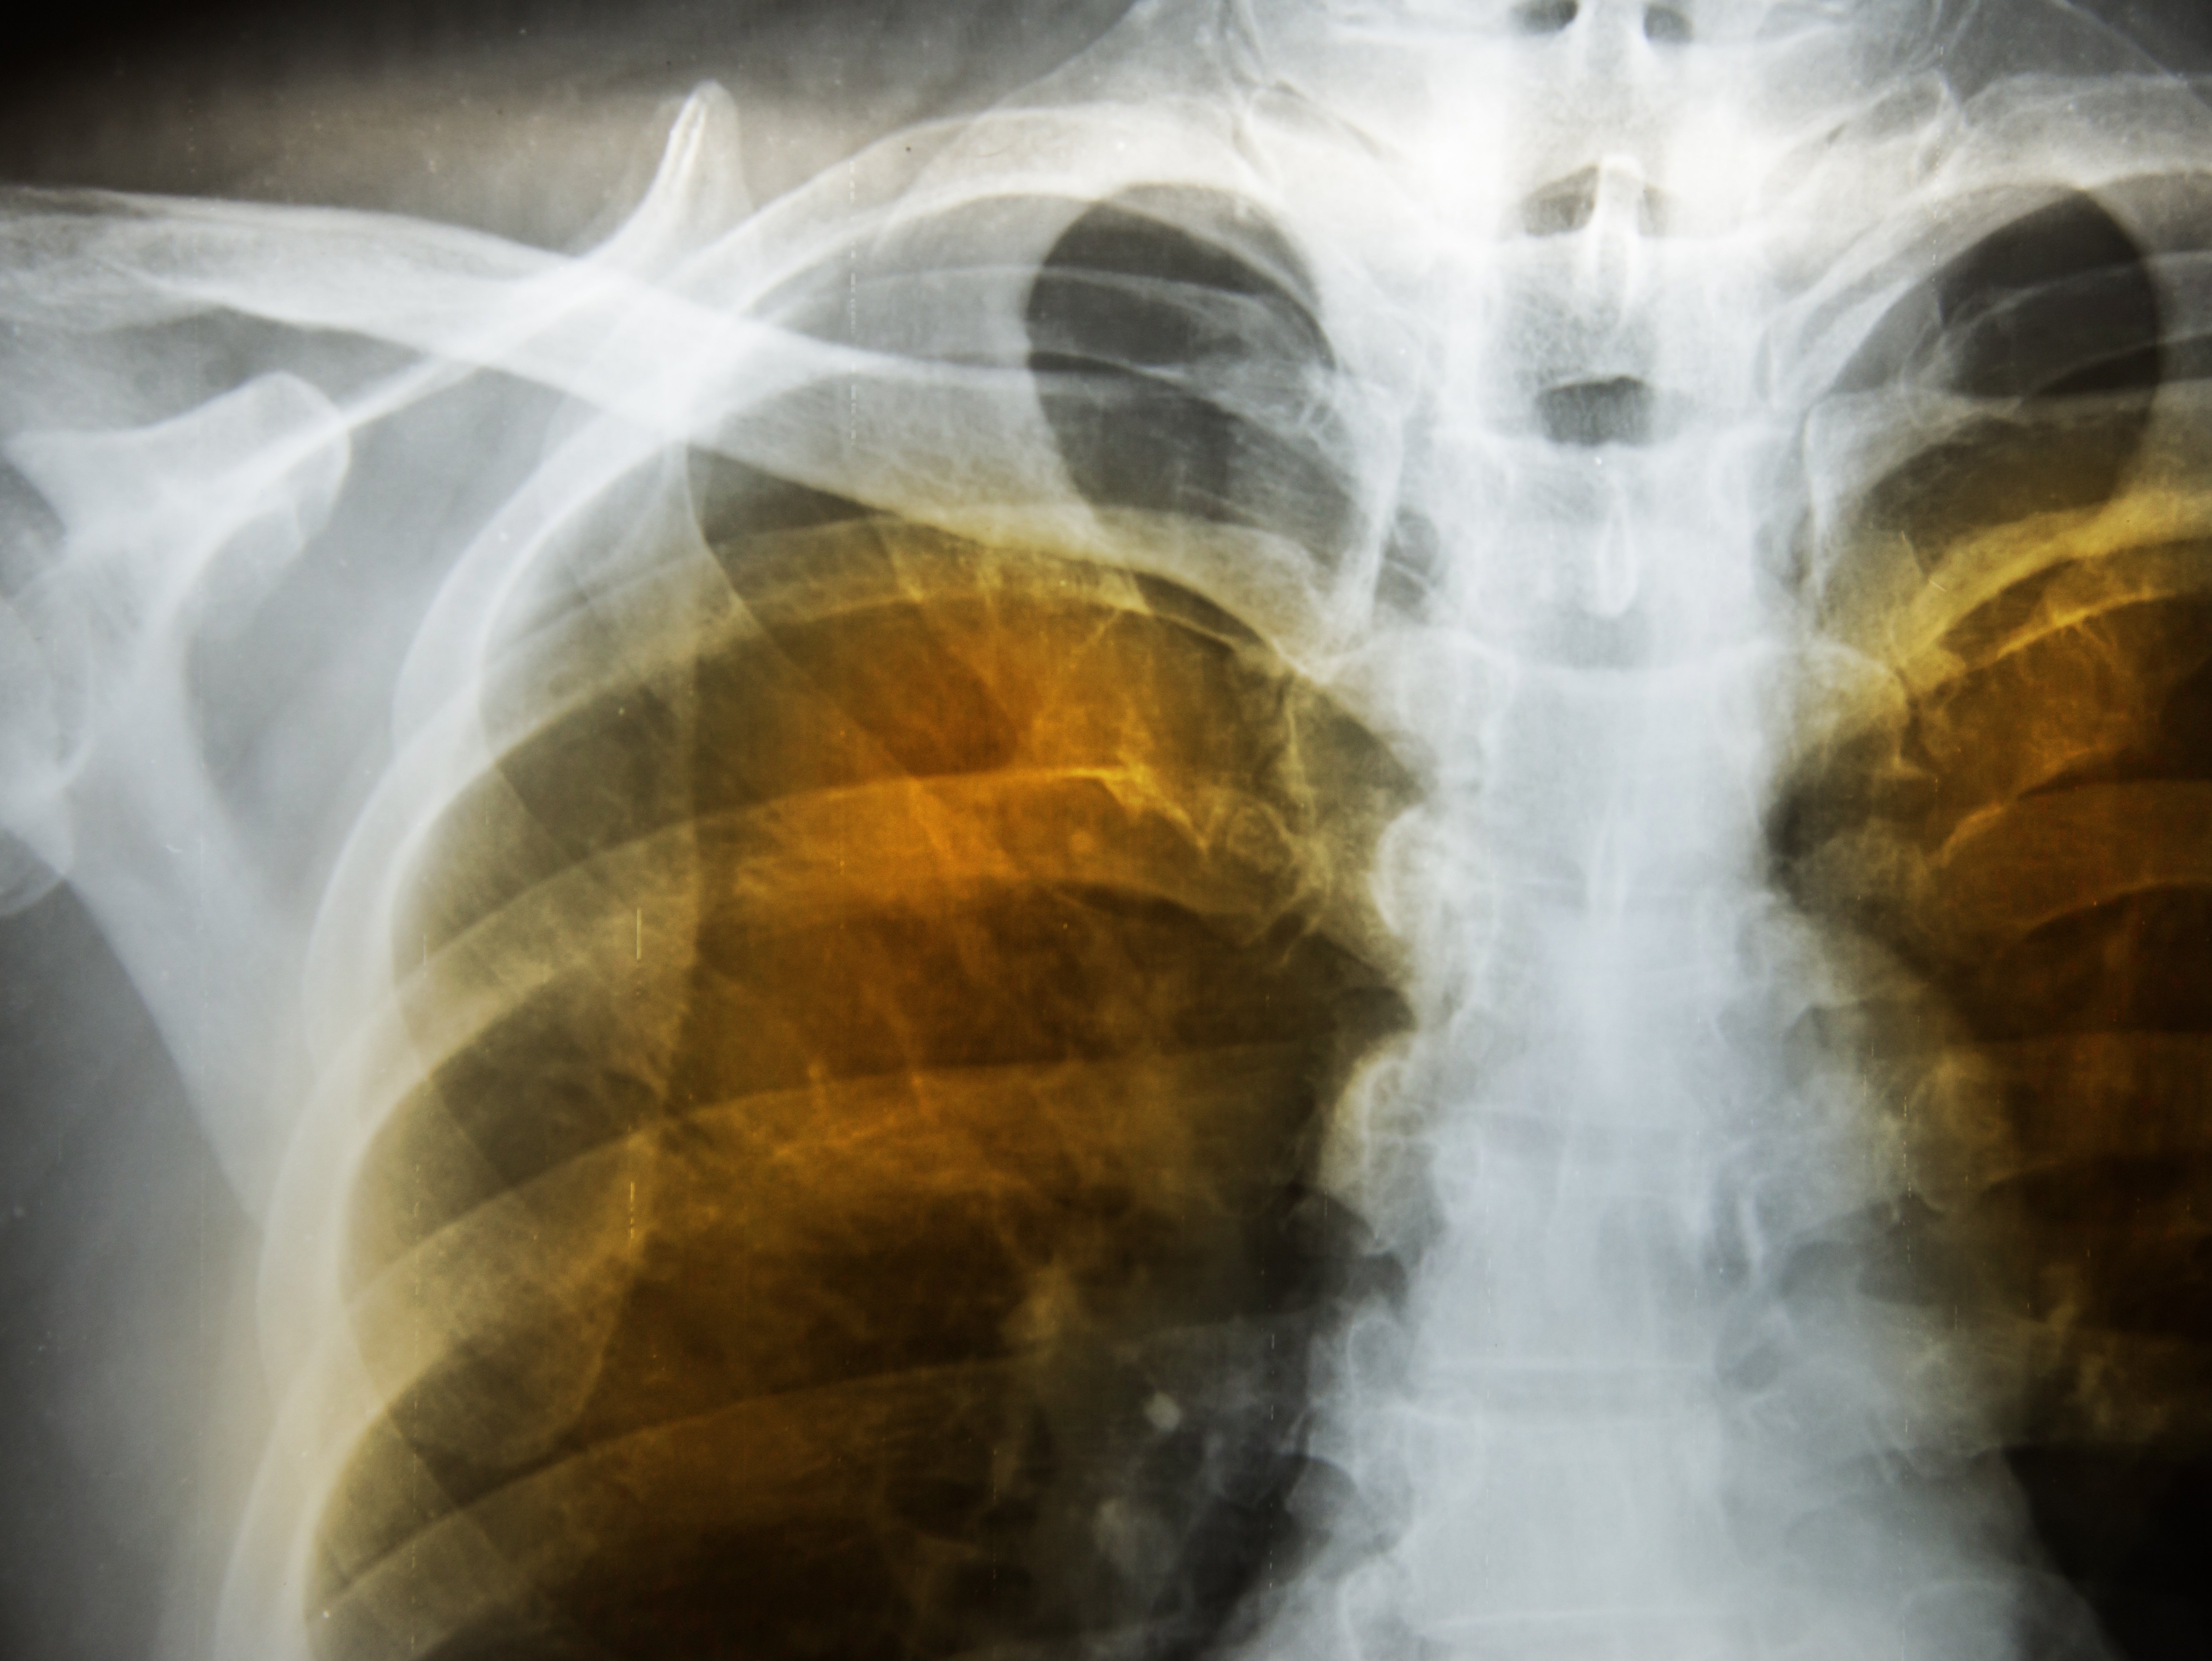

COPD, a progressive lung disease, encompasses chronic bronchitis and emphysema, leading to breathing difficulties and reduced lung function. In this blog, we will explore how heat, humidity, and summer ailments such as pollution can exacerbate the symptoms of COPD, impacting the quality of life for those affected.

Chronic obstructive pulmonary disease (COPD) is a prevalent and progressive lung disease that affects millions of people worldwide. It encompasses chronic bronchitis and emphysema, which lead to persistent airflow limitation and breathing difficulties. COPD is primarily caused by long-term exposure to harmful substances, such as cigarette smoke, air pollution, and occupational hazards.